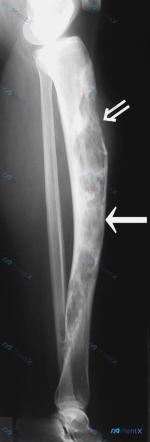

病例资料整理 患者信息:女性,21 岁。 主诉:腿部疼痛和畸形持续 7 年。 现病史:14 岁时发现异常,至今病程 7 年。 影像学检查: 1. X 光(14 岁及当前):胫骨骨干大范围溶骨性骨质破坏,呈膨胀性改变,骨皮质变薄,内部可见骨纹理消失及残留骨嵴(多房样改变)。侧位片可见胫骨前侧软组织轮廓...